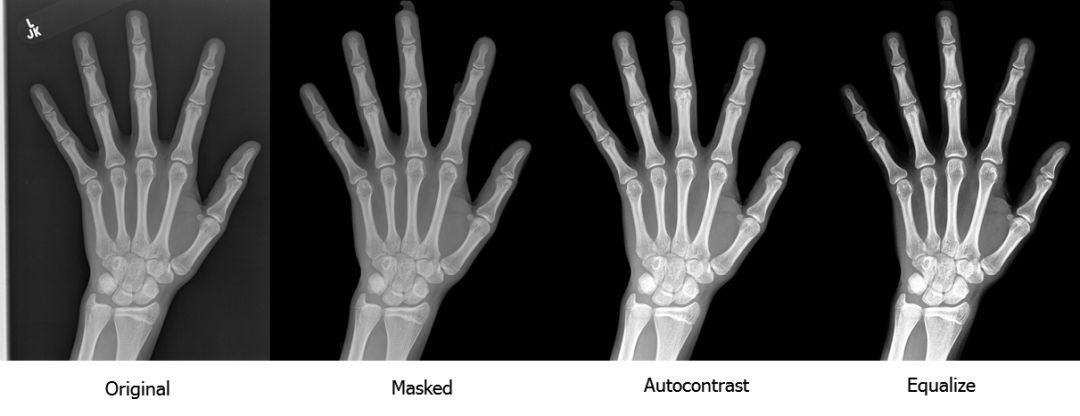

预处理 I:分割和对比 我们工作的关键贡献之一是进行了严格的预处理。为了防止模型因图像伪影学习到错误信息,我们首先通过图像分割来移除图像背景。 我们用 U-Net 深度架构(https://arxiv.org/abs/1505.04597)进行图像分割。自 2015 年 U-Net 出现以来,它就成为分割任务中的主力。它由一个获取上下文信息的收缩路径(contracting path)和一个用于精准定位的对称扩张路径(symmetric expanding path)组成;因为本文主题不是 U-Net,我们简单地展示一下其架构即可,细节请参阅论文。

我们还在训练过程中使用了批归一化使函数收敛。我们的算法使用的是广义损失函数(generalized loss function) 式中 H 是标准的二进制交叉熵损失函数 ,式中 y_i 是像素 i 的真值, 是像素的预测概率,J 是 Jaccard 系数的可微泛化: 。 我们通过移除小的无关的连接组件和均衡对比度完成了分割步骤。下图是我们进行预处理的流程:

如你所见,放射图像的质量和对比度有了显著的提升。你可以到这里停止预处理,用我们的预处理方法和标准技术(如缩放和旋转)来增强训练集,然后训练一个标准的卷积神经网络用于分类或回归。我们试了这种方法,尽管结果不如我们的最终模型,但是也很令人满意。 之前的 GP 和 TW 方法关注的是手骨的特定部位(包括指骨、掌骨和腕骨)。我们决定试着用这些信息,针对几个解析度较高的特定区域分别训练模型,再评估和比较它们的性能。为了正确定位这些区域,我们要将所有图的大小和位置转换成一样的,也就是说将它们放在相同的坐标空间中,该过程通常被称为图像配准(image registration)。 预处理 II:基于特征点进行图像配准 我们的图像配准策略很简单:检测手骨中几个特征点的坐标,然后计算仿射变换参数(缩放、旋转、平移和反射),使图像与标准位置一致。 为了创建特征点模型的训练集,我们用 VGG 图像注释器(VIA)手动标注了 800 张放射影像。我们选择了三个特征点:第三根手指远端指骨的顶端,拇指远端指骨的顶端以及头状骨的中心。我们将特征点的像素坐标作为回归模型的训练目标。 再说一次,特征点模型是受一系列 VGG 族模型启发、通过深度卷积神经网络实现的回归模型。VGG 模块由两个带有指数线性单元激活、批归一化和最大池化的卷积层组成。下图是其架构: